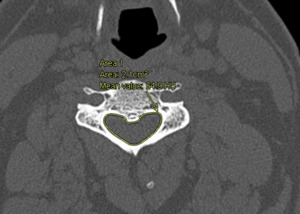

IPD, APD, and spinal canal area were assessed in patients who met inclusion criteria. Window and level specifications of 2,000 Hounsfield Unit (HU) and 500 HU were applied, respectively. Figure 1 demonstrates the evaluation of APD and IPD, while Figure 2 portrays the CCC area. APD was defined as the anterior-to-posterior distance at the midline of the central canal. IPD was defined as the maximum distance between the medial aspect of the pedicles at a specific vertebral level. The canal area was manually measured using the AGFA Enterprise Imaging markup freeform tool. Subsequently, an estimated area of the CCC was calculated using elliptical, triangular, and rectangular approximations. This was conducted using Equations 1-3 respectively. Equations 4 - 8 were used to apply SOAs developed from patients without the diagnosis of CCC stenosis. All equations are depicted in Figure 3.